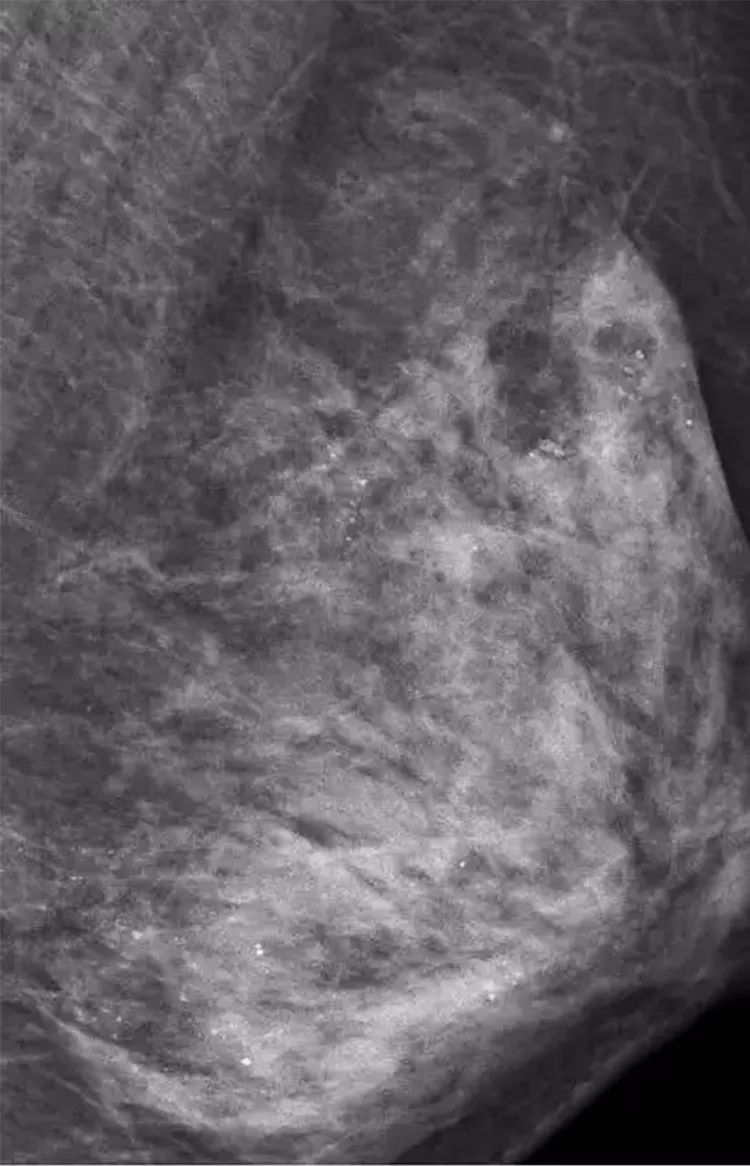

医生在X线检查时,意外地发现,她的左侧乳房乳腺里布满数不清的“沙粒”,全是细小如沙子的钙化灶。

乳腺沙砾样钙化灶是乳癌的信号之一,而当医询问到病史时,她表示,